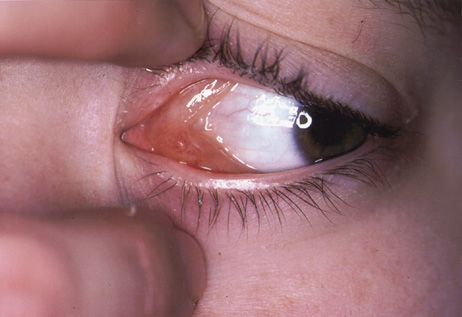

One-third of all orbital capillary hemangiomas are noted at birth, and virtually all are diagnosed by age 6 months.10 Most commonly a unilateral diffuse subcutaneous or circumscribed, dimpled, red dermal lesion (strawberry nevus) is noted on the upper eyelid (Figs. 1 and 2).9,10 In more than one-third of patients, the palpebral or fornical conjunctiva is involved.10 Commonly, this superficial lesion is associated with a component deep to the orbital septum resulting in variable degrees of proptosis in 38% of patients.10 More rarely, it can occur as an isolated lesion posterior to the orbital septum without a superficial component: In Haik and colleagues' large series of 101 infants with capillary hemangiomas, seven presented with proptosis alone.10 Forty-six percent of patients have an increase in lesion size with crying or Valsalva maneuver.10 Very rarely, hemangiomas can occur within the extraocular muscles.15 Early flat, circumscribed lesions rapidly expand into bulky, compressible masses over a period of weeks to months as the capillary lumina of the endotheliomatous hamartoma opens.16 This distinguishes the capillary hemangioma from the port-wine stain (nevus flammeus) associated with the Sturge-Weber and Klippel-Trenaunay syndromes, which remains flat to slightly thickened and is noncompressible. The infantile capillary hemangioma usually reaches its largest size within 6 months and then typically involutes.10,17 Fine, stellate areas of pale scarring (herald spots) appear during resolution (Fig. 3). Residual pigmentary skin changes and superficial cutaneous scarring may result.10 The most common ocular complication of adnexal capillary hemangiomas is visual loss, most often resulting from amblyopia or in rare cases optic atrophy. Amblyopia occurs in 44% to 64% of these infants and usually is a result of anisometropia, visual deprivation, or both.9,10,18 Anisometropia may result from axial myopia induced by the eyelid closure or astigmatism (plus cylinder axis points toward the tumor mass).19 Strabismus may be present in up to 34% of patients with periorbital infantile capillary hemangioma.18 Associated dermal or visceral hemangiomas throughout the body have been reported in 29% of infants with periorbital capillary hemangiomas.10 Laryngeal hemangiomas are the most frequent visceral vascular manifestation. In rare cases, hepatic, gastrointestinal, or intracerebral hemangiomas may be present.20 Sequestration of platelets and red blood cells leading to thrombocytopenia and bleeding diathesis (Kasabach-Merritt syndrome) can occur with large visceral lesions but are rare with isolated head and neck lesions.10,21